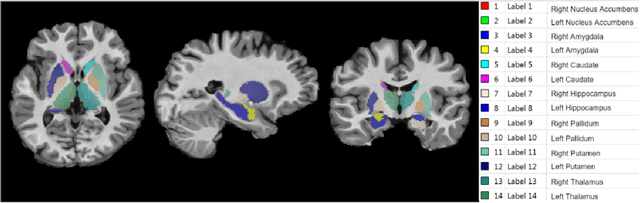

Abstract:Segmentation of sub-cortical structures from MRI scans is of interest in many neurological diagnosis. Since this is a laborious task machine learning and specifically deep learning (DL) methods have become explored. The structural complexity of the brain demands a large, high quality segmentation dataset to develop good DL-based solutions for sub-cortical structure segmentation. Towards this, we are releasing a set of 114, 1.5 Tesla, T1 MRI scans with manual delineations for 14 sub-cortical structures. The scans in the dataset were acquired from healthy young (21-30 years) subjects ( 58 male and 56 female) and all the structures are manually delineated by experienced radiology experts. Segmentation experiments have been conducted with this dataset and results demonstrate that accurate results can be obtained with deep-learning methods. Our sub-cortical structure segmentation dataset, Indian Brain Segmentation Dataset (IBSD) is made openly available at \url{https://doi.org/10.5281/zenodo.5656776}.